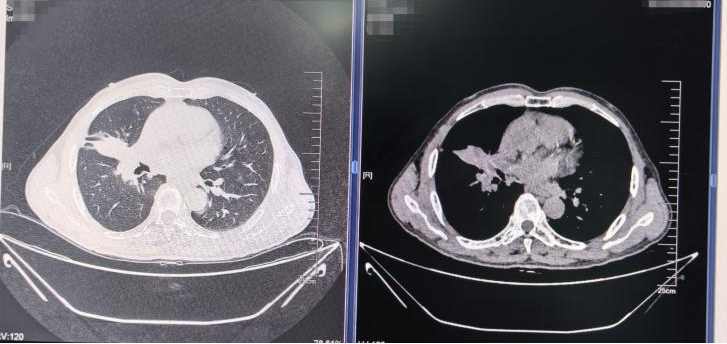

2024年8月21日,查头颅+胸部增强平扫CT:与2024-3-28对比,1.病灶横截面范围约:7.4cm×6.4cm×6.5cm;2.右肺中叶-肺门区肿瘤性病变(肺癌)合并空洞形成;3.纵膈多发淋巴结,部分肿大;4.寰椎,驱椎骨质破坏伴寰驱关节失稳,颈髓鞘受压,提示肿瘤性病变;5.双侧颈部多发淋巴结,部分肿大钙化等

胸部增强CT(2024-08-21)

2024年10月11日复查头颅+胸部增强平扫CT示:与2024-8-21对比,右肺中叶-肺门区占位范围较前缩小,空洞阴影较前缩小,璧相对稍变薄,右肺中上叶炎性病变较前缩小,纵膈淋巴结部分较前缩小,其余示大致同前。

2025年6月28日复查头颅+胸部增强平扫CT示:病灶与不张的肺组织整体范围约 5.2cm×2.3cm×2.1cm(原7.4cm×6.4cm×6.5cm),右肺中叶支气管狭窄,局部闭塞,紧贴临近血管)。

胸部增强CT(上:2024-08-21 vs 2024-10-11 vs 2024-11-24 vs 2025-03-18 vs 2025-06-28;下:2025-08-27)